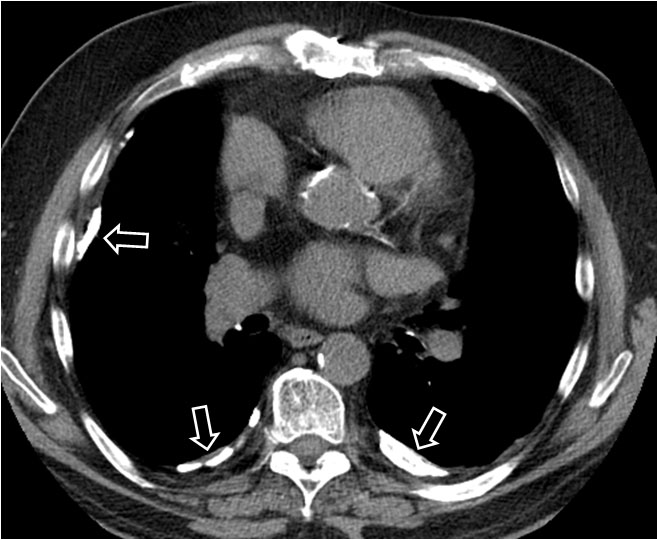

Este signo nos permite diferenciar entre derrame pleural y ascitis en un estudio de TC. Cuando existe una interfase nítida entre líquido y el hígado o el bazo, se trata de ascitis; cuando la interfase no es nítida, se trata de derrame pleural (flecha). El derrame pleural ocupa una posición más posterior y medial, mientras que la ascitis se localiza anterior y lateral al hígado y al bazo.

SIGNO DEL ÁREA DESNUDA

Cuando en la TC vemos líquido en situación dorsal al hígado (flecha), éste se encuentra en la cavidad pleural, ya que el líquido intraperitoneal no puede acumularse en esta zona debido a que el peritoneo se repliega sobre la cúpula hepática sin llegar a cubrir la parte posterior del hígado, es decir, que no hay cavidad peritoneal por detrás del hígado y, por tanto, la ascitis no puede ocupar este espacio.

En esta imagen también está presente, lógicamente, el Signo de la interfase.

SIGNO DE LAS CRURAS O DEL PILAR DIAFRAGMÁTICO DESPLAZADO

Cuando en la TC vemos que las cruras diafragmáticas están desplazadas lejos de la columna por líquido, éste está situado en la cavidad pleural (flecha). El líquido intraabdominal, a diferencia del derrame pleural, se sitúa lateral y anterior a las cruras.